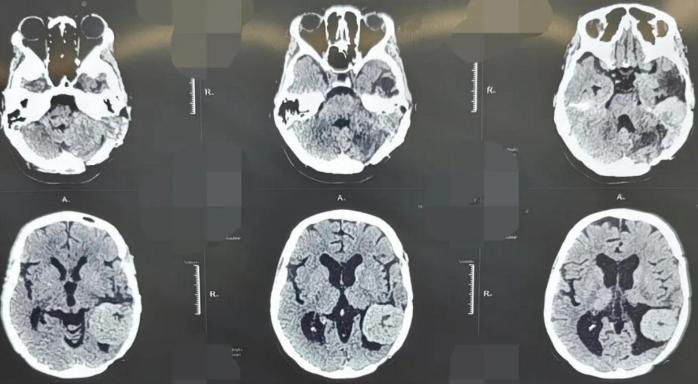

45岁的患者张女士,因“头晕、耳鸣伴听力下降”来到西安市红会医院就诊。她曾在2011年和2017年两次因颅内血管周细胞瘤于外院接受开颅手术治疗,并进行术后放化疗。此次入院后影像学检查显示,肿瘤在左侧颞部及桥小脑角区复发。该区域毗邻脑干、面神经、听神经及多条重要血管,素有“生命禁区”之称,手术风险极高。

更为严峻的是,进一步检查发现患者体内存在高度疑似肝脏转移灶,提示疾病可能已进入晚期;同时合并严重贫血、心脏电生理异常等多种并发症。病情复杂、风险叠加,任何环节处置不当均可能导致严重后果。